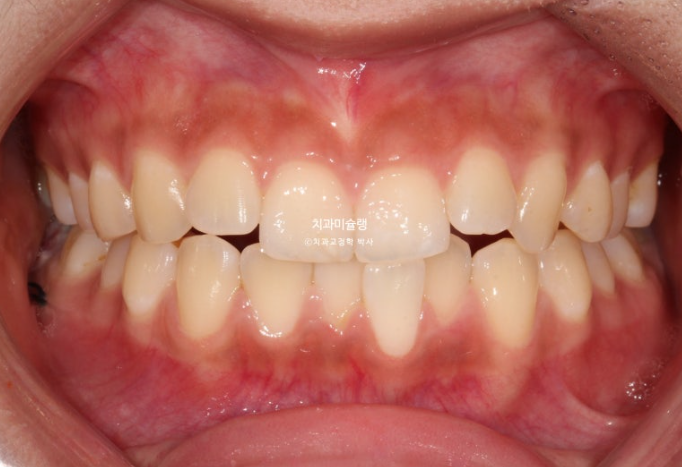

24년 여름방학을 이용해서 교정상담을 온 유학생 환자분입니다.

측절치의 개방교합, 아래 앞니 덧니 등 보입니다.

우측 교합관계는 1급에 가깝지만

좌측 교합관계는 2급입니다.

위 아래 치아들이 일대일로 물리면 2급 또는 3급 교합관계 입니다.

송곳니에서 큰어금니까지 절반씩 엇갈려 물리는 교합이 1급 교합입니다.